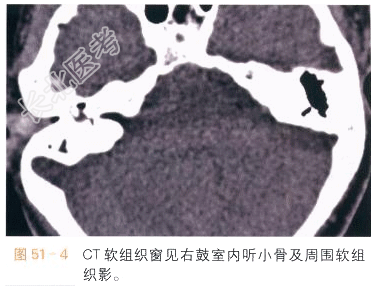

影像学资料如图51-1~图51-4所示。

单纯性中耳炎CT扫描可见鼓室、乳突少许渗出,鼓室和乳突气房模糊、密度增高。MR检查见鼓室、乳突少许渗出积液,严重者可见听小骨和听骨链周边模糊、硬化、变小,甚至消失。若CT扫描发现鼓室黏膜增厚,鼓室-鼓窦-乳突区见不规则软组织影,边界欠清,周边骨质受压侵蚀、吸收,如图51-1~图51-4所示,则要考虑有胆脂瘤或胆脂瘤性肉芽肿形成。由于胆脂瘤或胆脂瘤性肉芽肿含脂质成分,因此在MR检查时T1WI呈等信号、T2WI等高信号,胆脂瘤性肉芽肿周边可轻度强化。